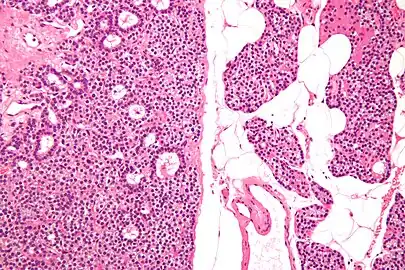

Micrograph of a parathyroid adenoma (left) and normal parathyroid gland (right). H&E stain.

Normal parathyroid gland with prominent adipose tissue is seen on the right of the image.-High magnification

Intermediate magnification